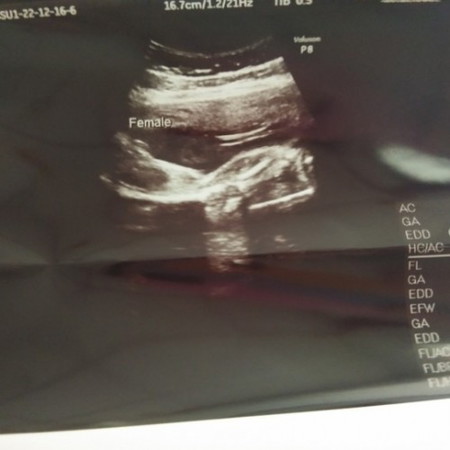

อยากให้แม่ช่วยดูหน่อยคะว่าน้องเป็นเพศ ญ.หรือ.ช.คะ

หมอบอกผู้หญิงค่ะ

ผู้หญิงค่ะ

ดีใจมากเลยค่ะ😊